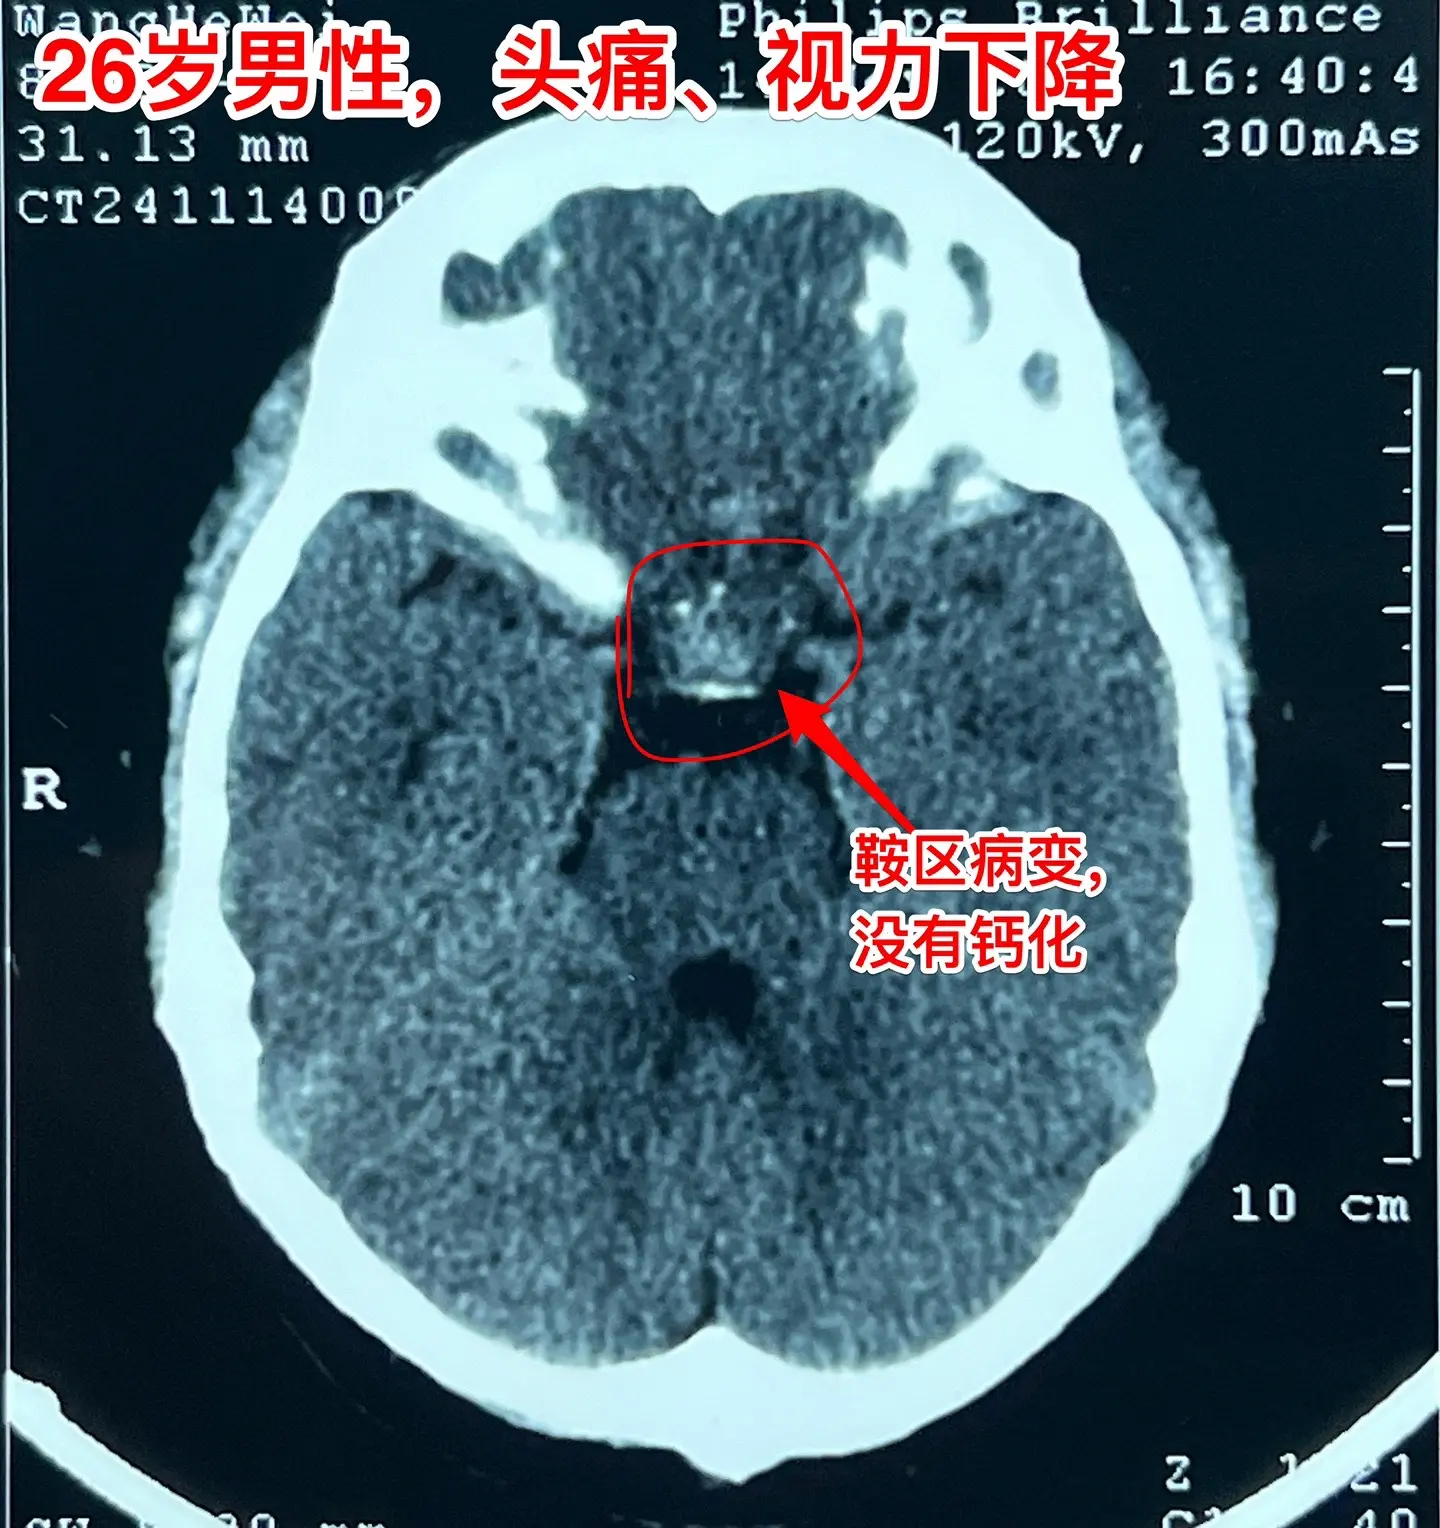

拉克氏囊肿的症状有时和颅咽管瘤是一样的。拉克氏囊肿不是真正的肿瘤,但是其发生的位置和颅咽管瘤很相似。通常情况下拉克氏囊肿的症状比较轻微,但是有的拉克氏囊肿体积大,对下丘脑-垂体的损害也很严重,产生明显的下丘脑-垂体功能障碍,同时也会压迫视神经产生视力下降,和颅咽管瘤产生的症状一样。 这个26岁的湖北孝感市小伙子有头痛、视力下降症状,化验显示也有垂体功能减退。所以有手术指征了。2024.11.22作了手术,将囊肿大部分切除,充分减压,尽可能地保留垂体柄和垂体的功能。